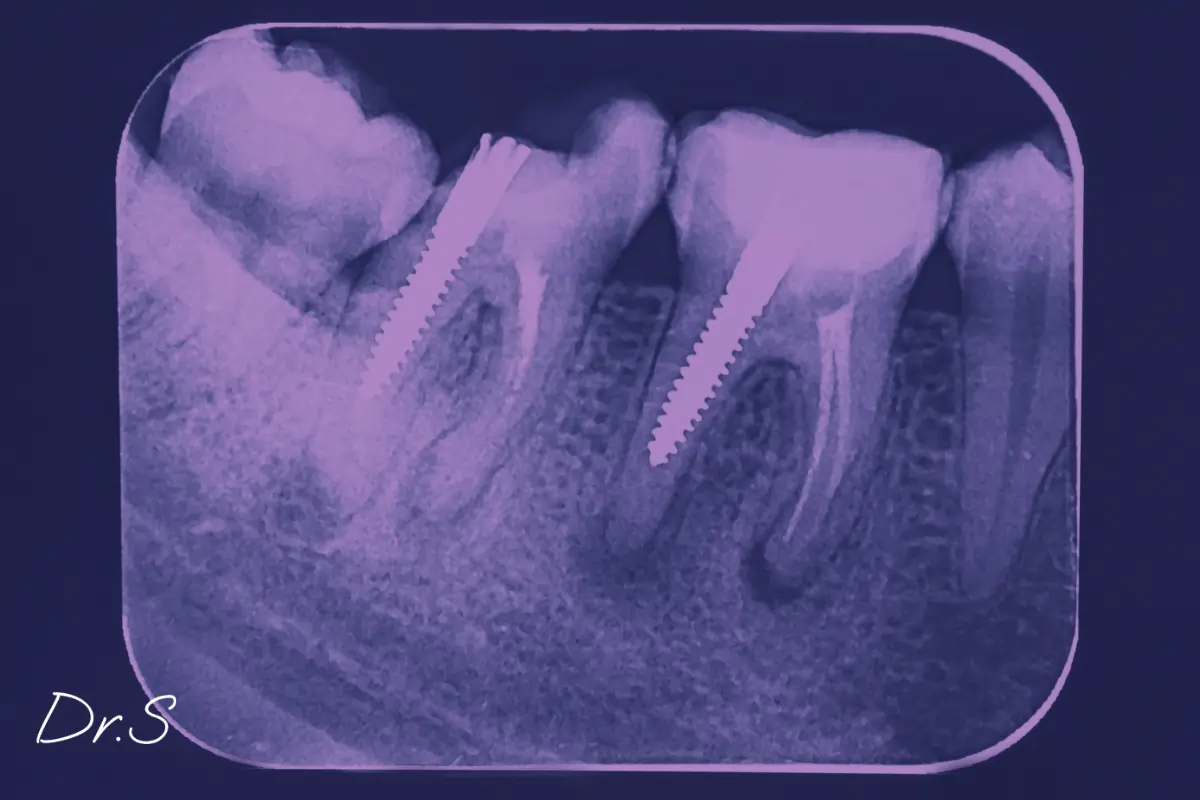

Je complète souvent par des tests de vitalité dentaire et, selon le cas, par des examens d’imagerie comme une radiographie panoramique ou un CBCT (scanner dentaire en 3D). Ces outils permettent de déceler des lésions invisibles à l'œil nu.

C’est par l’imagerie que l’on identifie le plus souvent ces foyers latents. Une radiographie panoramique permet une vue d'ensemble. Un CBCT offre un niveau de détail plus élevé, en trois dimensions.

On parle de foyer infectieux latent lorsqu’il existe une infection chronique, mais sans douleur ni manifestation aiguë. Cela peut concerner une dent dévitalisée infectée, un granulome apical (petite infection au bout de la racine), un kyste ou une zone de mobilité dentaire non ressentie.